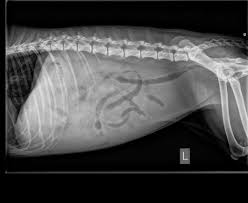

Der erste Tierarzt vermutete einen Herzfehler der zweite bei dem das Röntgenbild erfolgte war sich nicht. Ein weiterer Grund warum sich Wasser in der Bauchhöhle bildet ist eine Störung des Lymphabflusses. Das Gleichgewicht zwischen Bauchwasserproduktion und Rückaufnahme kann jedoch aufgrund verschiedener Erkrankungen aus der Balance geraten.

Laut Röntgenbild hatte es sehr viel Wasser in der Bauchhöhle. Infektionen wie zum Beispiel Tuberkulose können auch zu einem Wasserbauch führen. Diese Flüssigkeitsansammlung bezeichnet man als Aszites oder Bauchwassersucht.